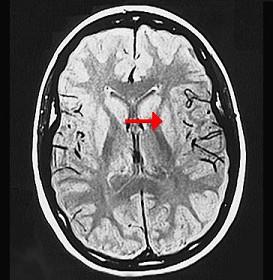

如图箭头所示为大脑哪个部位 ( )A、内囊B、齿状核C、丘脑D、尾状核E、壳核一、单项选择题

问题 如图箭头所示为大脑哪个部位 ( )

选项 A、内囊 B、齿状核 C、丘脑 D、尾状核 E、壳核 一、单项选择题

答案 E